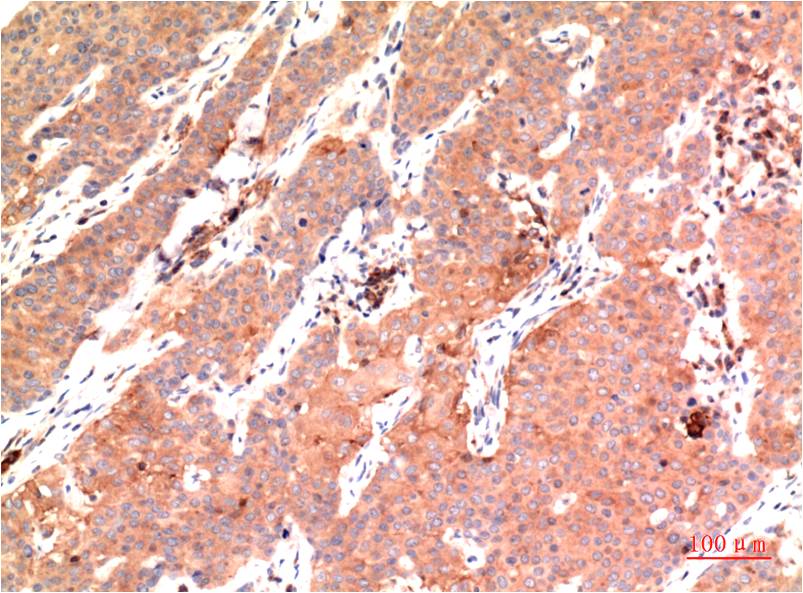

IHC 1/50-1/100 Human,Mouse,Rat